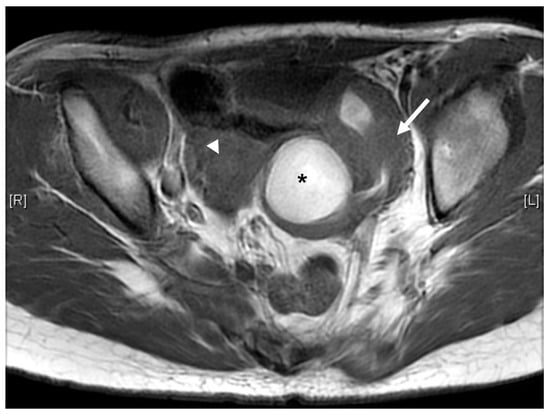

Case 3 was a female infant born at 34 weeks of gestation. The antenatal ultrasound showed fetal ureteral obstruction and oligohydramnios. She had a poorly developed vestibule with a small orifice near the clitoris and high-type imperforate anus, indicating cloacal malformation. A double-barrel colostomy and drainage of 30 mL turbid urine of the orifice of the common channel, possibly from the distended vagina, was performed at 5 hours of age. Abdominal ultrasound at 1 day of age showed a 7.5 cm cystic mass in the lower abdomen, but it decreased in size on the next day. Water instillation via urinary catheter visualized the urinary bladder and enlarged the cystic mass on real-time ultrasound, suggesting HMC with vesicovaginal fistula. The patient received spinal lipoma excision at 8 months of age for the lipomyelomeningocele, and repair for tetralogy of Fallot at 1 year of age. Posterior sagittal anorectovaginourethroplasty using the Pena method was performed at 1 year, 8 months of age, and the distal vagina was replaced by a 5 cm length of rectum. She began menstruating at 12 years, 10 months, which was associated with cyclic abdominal pain, and the MRI detected uterine didelphys with left hematometrocolpos, hemivagina, and left renal agenesis (Figure 4 and Figure 5). Hysteroscopy was performed via the neovagina, and one bulging mass in the left side was observed. The right uterus cavity was normal with smooth endometrium. Herlyn–Werner–Wunderlich syndrome was diagnosed. The patient anticipates left hemi-hysterectomy and transcervical resection of the vaginal septum.

Figure 5.

MRI of case 3: left renal agenesis and right hydroureter.